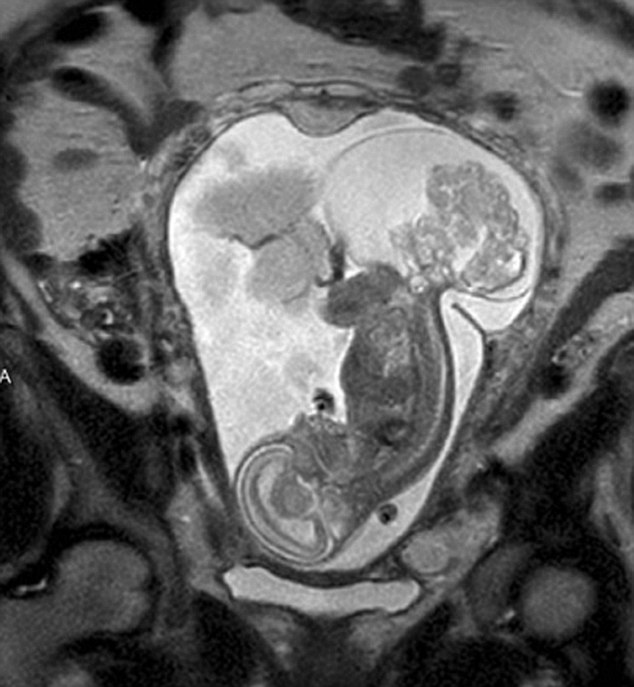

Οι γιατροί ανακάλυψαν ότι το αγέννητο μωράκι της Margaret Boemer είχε όγκο στον υπέροχο των 16 εβδομάδων. Έπρεπε να υποβληθεί σε επέμβαση για να καταφέρει να ζήσει. Άνοιξαν τη μήτρα και αφαίρεσαν το κοριτσάκι για 20 λεπτά για μια εγχείρηση ζωής ή θανάτου και μετά το έβαλαν ξανά στη μήτρα της Margaret.

Όταν δόθηκε το πράσινο φως στους χειρουργούς, η LynLee ήταν σχεδόν 24ων εβδομάδων και ο όγκος είχε το ίδιο μέγεθος με το κοριτσάκι. Η επέμβαση διήρκησε 5 ώρες, με τον Dr Cass να τονίζει πως είναι ένα είδος θαύματος να ανοίγεις τη μήτρα, να την κλείνεις και όλο αυτό να λειτουργεί. Οκτώ μέρες μετά τη γέννησή της η μικρούλα LynLee βρέθηκε ξανά στο χειρουργείο προκειμένου οι γιατροί να αφαιρέσουν μικρά τμήματα του όγκου που δεν μπόρεσαν να αφαιρέσουν την πρώτη φορά και είχαν αρχίσει πάλι να αυξάνονται.